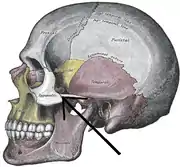

Still image (red) Side view of the skull. (Zygomaticotemporal suture is suture between zygomatic bone, at left in white, and temporal bone, at center in pink.)

Side view of the skull. (Zygomaticotemporal suture is suture between zygomatic bone, at left in white, and temporal bone, at center in pink.)